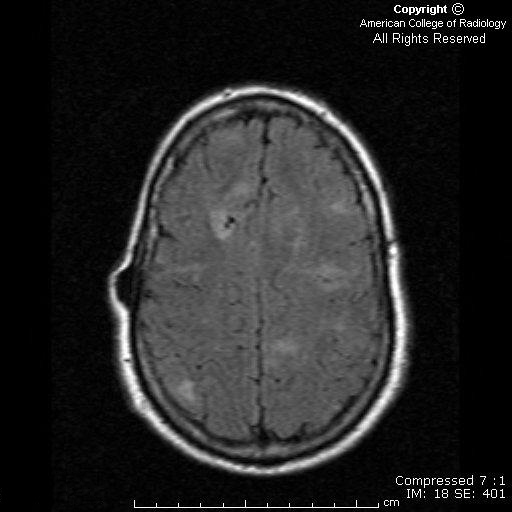

There are enhancing subependymal nodules (Figure 3) with the largest having degenerated into a subependymal giant cell astrocytoma (Figure 1 and Figure 2). There are multiple cortical/subcortical tubers seen best on FLAIR images (Figure 4).

Characteristic neurologic findings are present in over 95% of patients diagnosed with tuberous sclerosis. The classic neurologic features are calcified subependymal nodules, subependymal giant cell astrocytomas, cortical and subcortical tubers, and white matter lesions along lines of neuronal migration. Subependymal nodules can progress into subependymal giant cell astrocytomas that can result in obstructive hydrocephalus at the foramen of Monro. Subependymal nodules and subependymal giant cell astrocytomas usually enhance on contrast studies and are often found along the caudothalamic groove. Periodic brain CT or MRI with contrast can be performed in asymptomatic patients to evaluate for development or progression of lesions that may eventually result in obstructive hydrocephalus. MRI fluid-attenuated inversion recovery (FLAIR) sequences are better for evaluation of subcortical and cortical tubers.